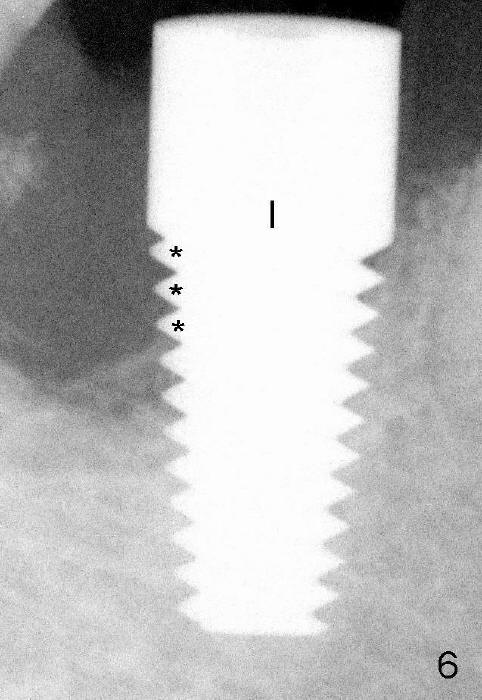

Finally, 7x17 mm implant is placed (Fig.6,6'). It appears that there is no bone contacting the top 3 threads of the implant distally (*). No bone graft is placed at the time of implant placement. It is thought that the existing infection may cause graft failure. With attention paid to eradicating socket infection (pre-, intra- and post-op antibiotic and removing granulation tissue after extraction), bone graft can be placed safely at the time of immediate implant.